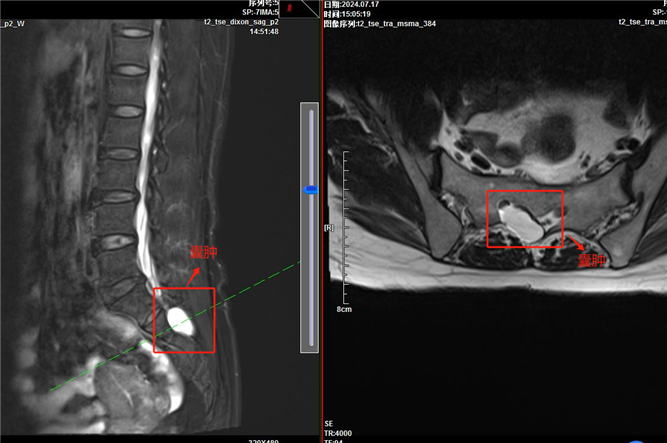

核磁顯示囊腫位置

這次來到晉城大醫(yī)院后,先就診于泌尿外科,泌尿外科了解病情后推薦她到疼痛科咨詢,本來打算放棄的趙阿姨,抱著“試一試”的心態(tài)到疼痛科,經(jīng)過相關檢查后,發(fā)現(xiàn)趙阿姨骶管有一個囊腫,壓迫到骶神經(jīng),導致會陰神經(jīng)痛。趙阿姨終于看到了希望!疼痛科的王萌醫(yī)生為她耐心講解會陰神經(jīng)痛的癥狀、治療方法,并立即確定手術方案。